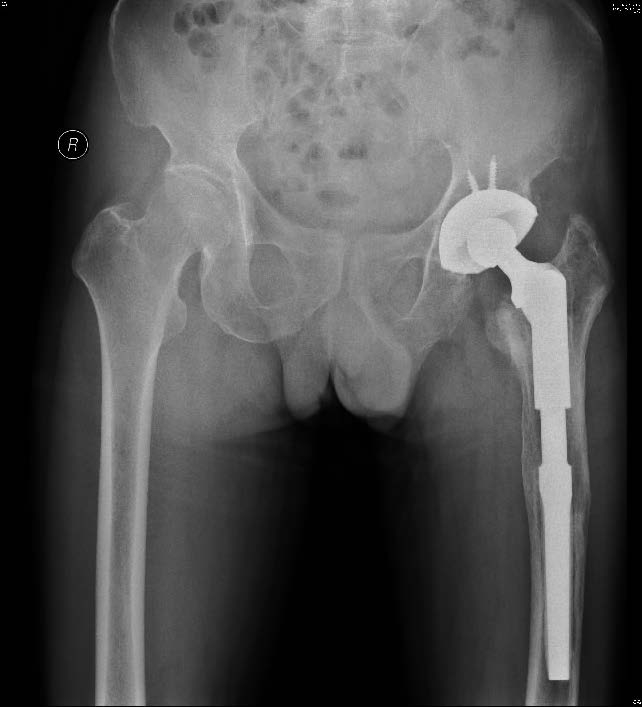

图3 同一患者,术后6 个月双髋X 线片示左侧MP 假体位置好、无松动

108例翻修患者中,有10例(9.3%) 取柄时出现骨折, 但均未出现大块骨折移位; 截骨16例(148%) ,其中骨水泥假体柄12例,非骨水泥假体柄4例,非骨水泥假体柄截骨均为大转子截骨,植入非骨水泥假体柄时未发生术中骨折及假体远端穿透皮质;9例假体力线不良,其中3例假体远端紧贴股骨外侧外皮质,均为柄尖端偏向外侧,复习术前X线片可见初次置换时即存在假体力线不良。所有骨折及截骨患者其中12例采用钛缆辅助固定。全组患者接受随访0.5~5年,平均33.4个月。术后X 线片评价假体在位(图2),术后3~6个月可见骨长入(图3),骨折线模糊或消失。末次随访时间Harris 评分和VAS 评分较术前分别为升高和降低,差异均有统计学意义(P值均<0.05),见表1。翻修所采用的3 种不同假体间翻修原因比较,差异也无统计学意义(P>0.05),见表2。初次手术不同固定方式间患者年龄、性别与VAS、Harris 评分的比较,差异均无统计学意义(P值均<0.05),见表3。